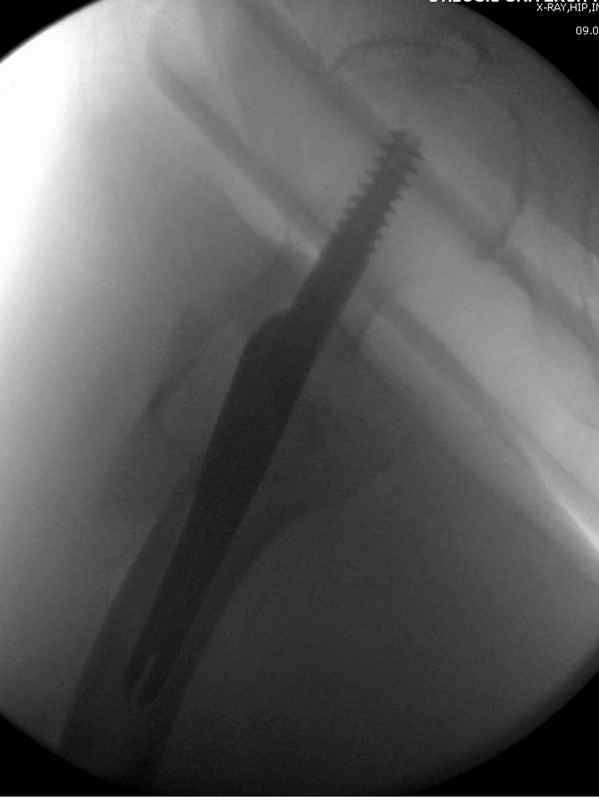

Здесь пара случаев фиксации похожих переломов:

первый высокоэнергетическая травма 36 лет

судя по картинкам с ЭОПа явно использовались приемы непрямой репозиции под его контролем, а так же интраоперационный ЭОП-контроль положения винтов, без такого контроля операция может ухудшить ситуацию (опять же учтите сроки) т.к. результат буде зависеть в большей степени от искусства хирурга, а не от технологии